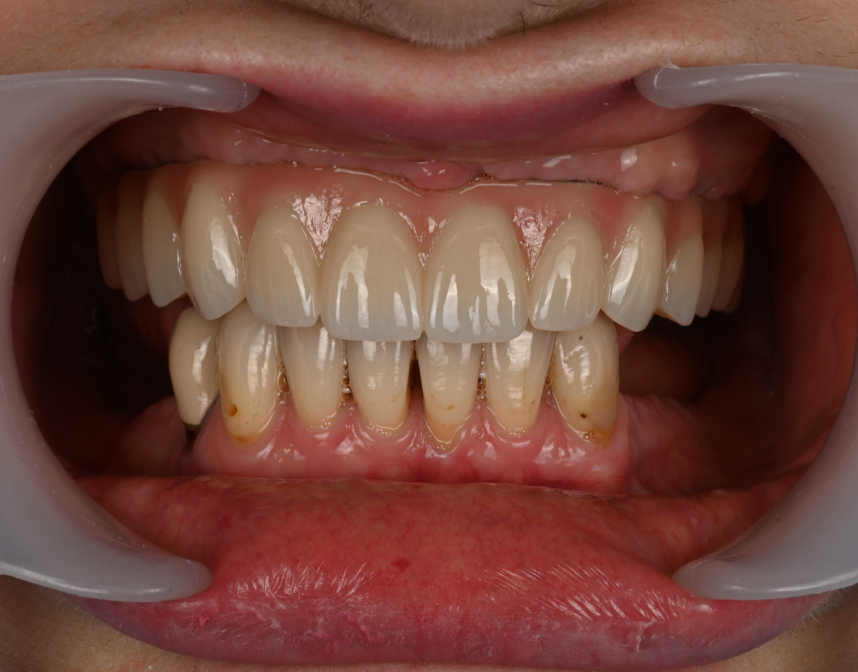

Cas cliniques

La réhabilitation globale est une solution complète pour ceux qui ont des problèmes de santé bucco-dentaire multiples et complexes. Elle consiste en un plan de traitement personnalisé, conçu pour traiter toutes les affections dentaires en une seule fois. Cette approche globale permet de restaurer l’harmonie du sourire, tout en améliorant la santé bucco-dentaire de façon durable.

Que vous souffriez de problèmes d’occlusion, de perte de dents, de maladie parodontale, ou d’autres problèmes dentaires, une réhabilitation globale pourrait être la solution pour vous. Au cabinet dentaire du Docteur Malthieu à Amiens, nous sommes fiers de pouvoir proposer cette approche intégrée à nos patients.